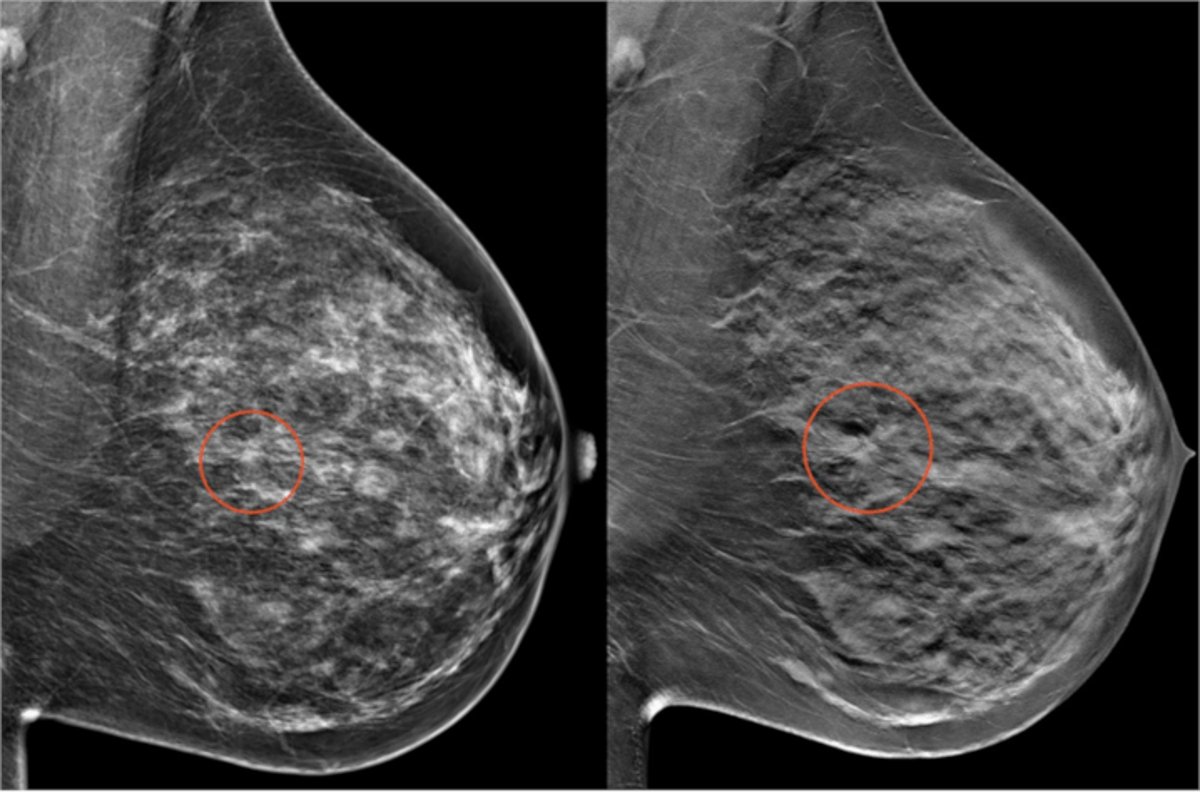

Las mastografías buscan detectar cambios o anormalidades en los tejidos del seno que con el tiempo pueden convertirse en problemas. Pueden descubrir pequeños nódulos o masas que no los puede sentir una persona. Si se descubre alguna anormalidad mediante la mastografía se requerirán estudios adicionales para descartar o confirmar el diagnóstico. En caso de que el resultado sea normal, se citará a una nueva mastografía en dos años.